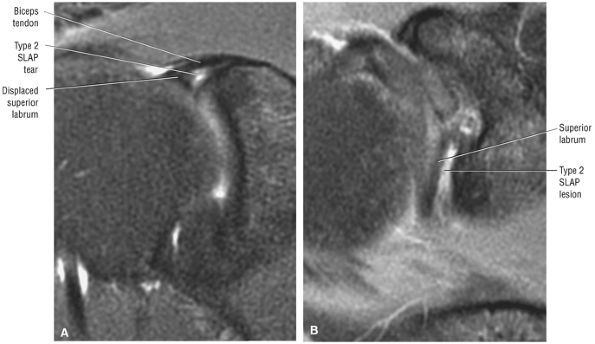

Type 2 SLAP tear extending primarily into the posterior superior labrum